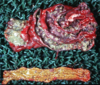

Q

This is a liver. What lesion is shown here?

A

multifocal hepatic abscesses